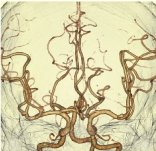

頭部脳血管VR -